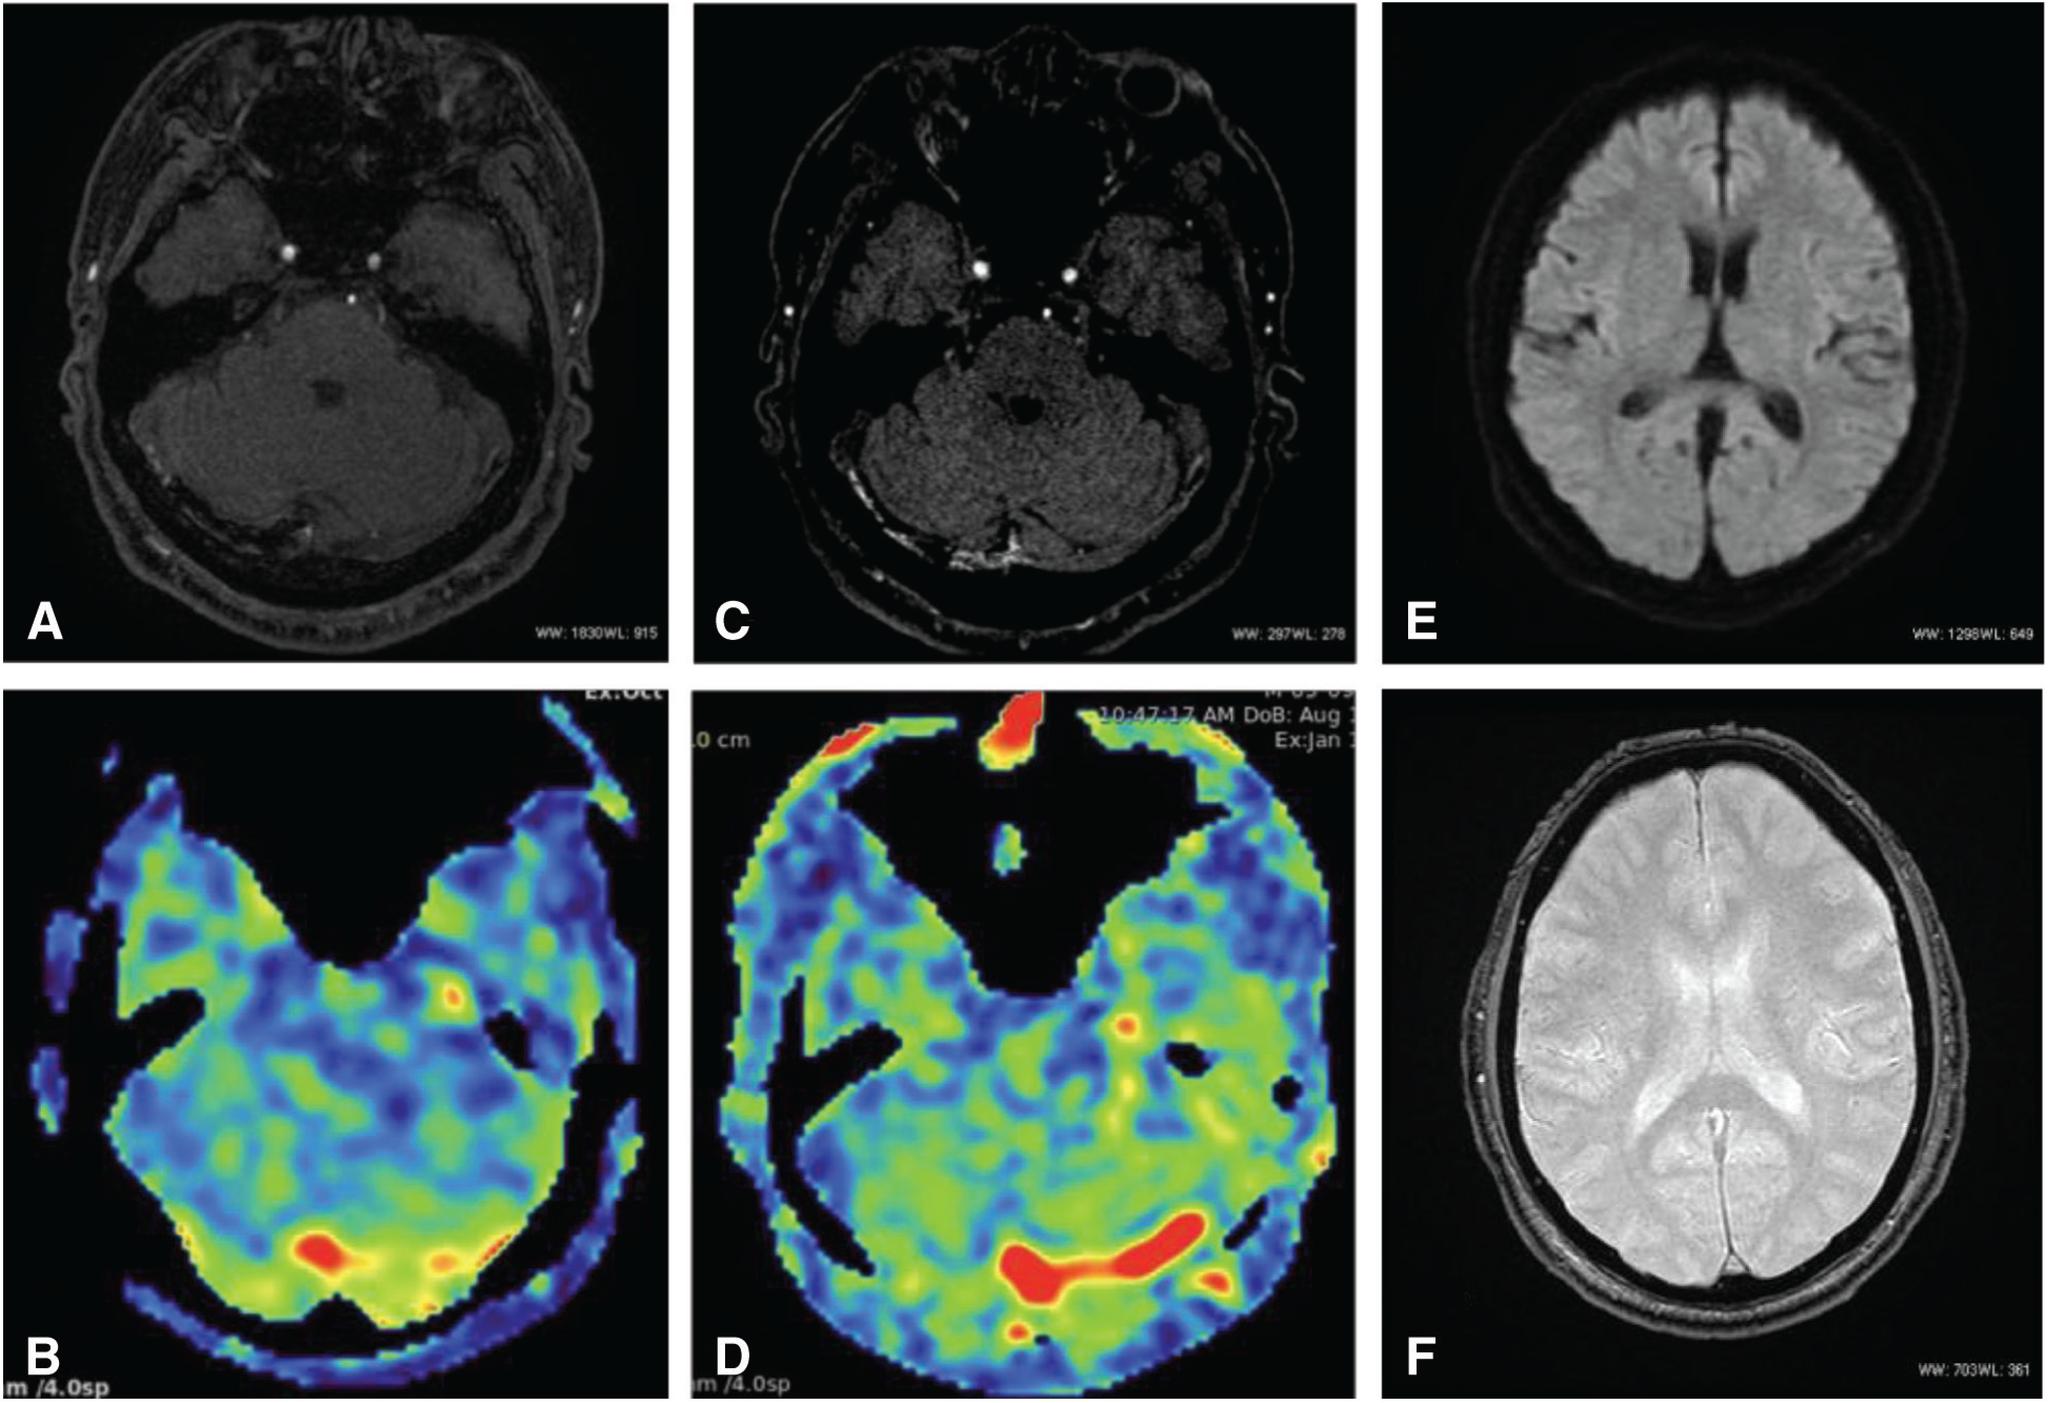

The patient was a 65-year-old man. Cerebral angiography demonstrated an aggressive dAVF involving the TSS, superior sagittal sinus (SSS), and the sinus confluence, with severe cortical and deep venous reflux. We performed multiple transarterial and transvenous embolizations for the TSS and sinus confluence lesion. The shunt disappeared almost completely after embolization. A high signal intensity that had been apparent in the SSS and straight sinus (StS) on ASL imaging before embolization disappeared after embolization. ASL imaging 3 months after embolization revealed slightly a high signal intensity in the StS, which was considered to be due to recurrence of the lesion. Moreover, recurrence of the confluence and TSS-dAVF was observed on cerebral angiography 6 months after embolization. As additional embolization was considered difficult, radiation therapy was recommended, but the patient refused; therefore, follow-up was performed. As ASL imaging findings were consistent with cerebral angiography findings, careful examination and monitoring of changes on ASL imaging were subsequently performed.

患者为一名65岁男性。脑血管造影显示为侵袭性硬脑膜动静脉瘘,累及横窦、上矢状窦(SSS)和窦汇,伴有严重的皮质和深部静脉逆流。我们对横窦和窦汇病变进行了多次经动脉和经静脉栓塞治疗。栓塞后分流几乎完全消失。栓塞前ASL成像中在SSS和直窦(StS)中明显的高信号强度在栓塞后消失。栓塞后3个月的ASL成像显示StS中有轻微的高信号强度,这被认为是由于病变复发所致。此外,栓塞后6个月的脑血管造影显示窦汇和TSS-dAVF复发。由于考虑再次栓塞困难,建议进行放射治疗,但患者拒绝;因此,进行了随访。由于ASL成像结果与脑血管造影结果一致,随后对ASL成像的变化进行了仔细检查和监测。